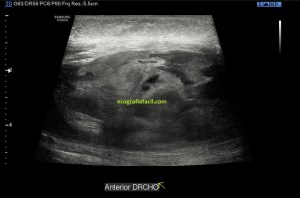

Cuando hice el corte longitudinal de la vesícula pude ver hasta tres patologías distintas, una adeomiomatosis (sin artefacto en cola de cometa), una litiasis vesicular y barro biliar, 2,3 y 4 respectivamente.

El caso no tiene mucho que explicar a no ser por la rareza de que se presente triple la semiología patológica en una misma imagen.

La adenomiomatosis, como un aumento de la ecogenicidad y el tamaño de la pared vesicular, la litiasis como una estructura hiperecogénica con sombra acústica posterior y el barro biliar, hiperecogénico rellenando toda la estructura ovoidea de la vesícula.

El cuello vesicular estaría afectado por la adenomiomatosis, el cuerpo por la litiasis y el barro ocuparía el fundas vesicular.